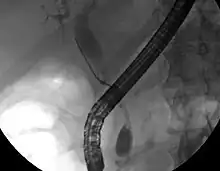

ERCP image of cholangiocarcinoma, showing common bile duct stricture and dilation of the proximal common bile duct

While abdominal imaging can be useful in the diagnosis of cholangiocarcinoma, direct imaging of the bile ducts is often necessary. Endoscopic retrograde cholangiopancreatography (ERCP), an endoscopic procedure performed by a gastroenterologist or specially trained surgeon, has been widely used for this purpose. Although ERCP is an invasive procedure with attendant risks, its advantages include the ability to obtain biopsies and to place stents or perform other interventions to relieve biliary obstruction.[12] Endoscopic ultrasound can also be performed at the time of ERCP and may increase the accuracy of the biopsy and yield information on lymph node invasion and operability.[55] As an alternative to ERCP, percutaneous transhepatic cholangiography (PTC) may be utilized. Magnetic resonance cholangiopancreatography (MRCP) is a non-invasive alternative to ERCP.[56][57][58] Some authors have suggested that MRCP should supplant ERCP in the diagnosis of biliary cancers, as it may more accurately define the tumor and avoids the risks of ERCP.[59][60][61]